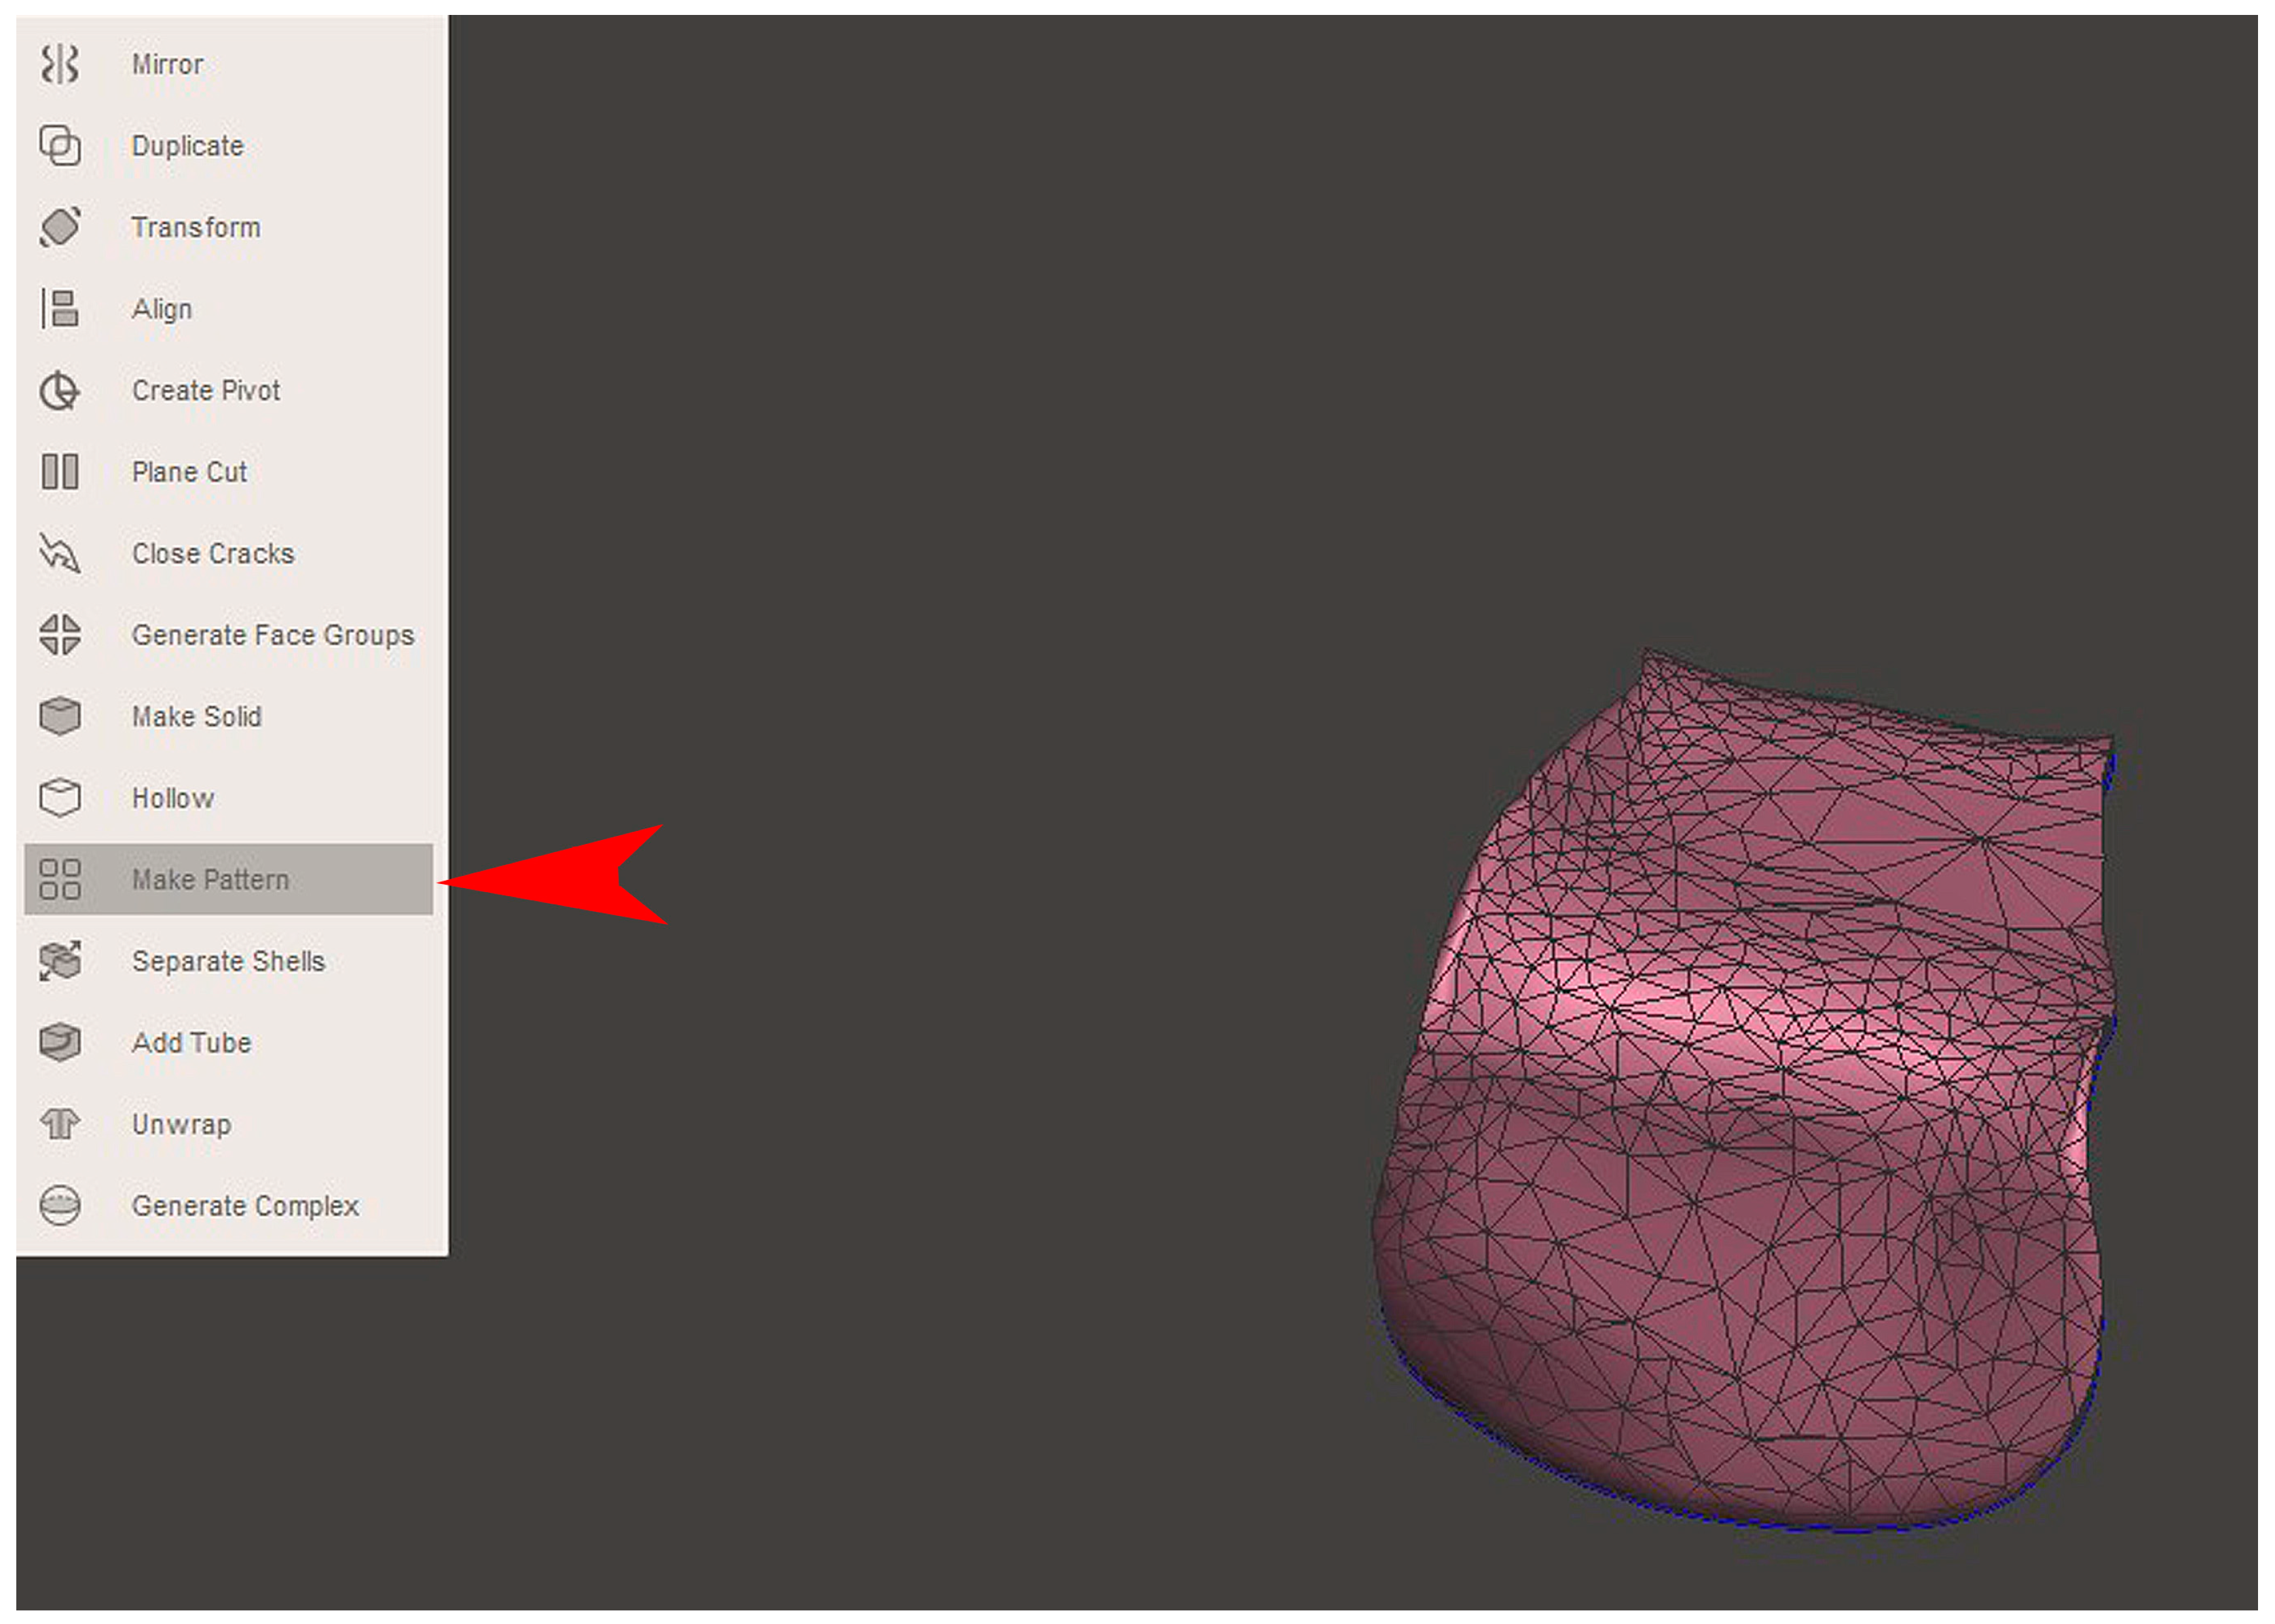

2.2. GBR Simulation and Mesh Design